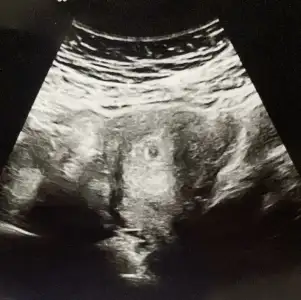

Bilmiyorum ki herkesin ki belirgin belirgin oluyo bisey gosterdi bak yeni olusuyo diye kizinca soramadim benden dahai iyi mi bilicen diye kizdi internetten bakip bakip geliyosunuz boş degil bu gebelik dedi 🤣🤣🤣🤣🤣🤣

IMG_20240502_205205.webp